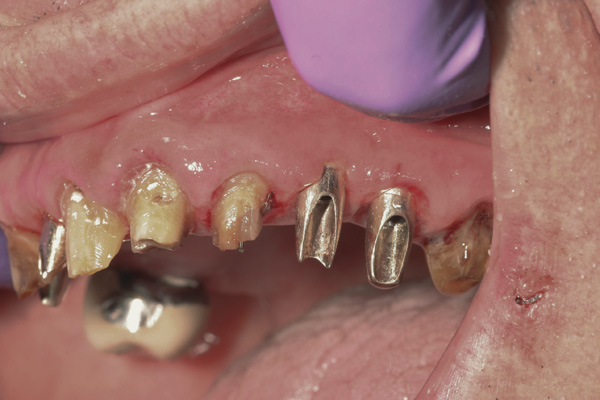

Background: This patient had a failing maxillary dentition and refused to wear a removable prosthesis. A staged approach was employed to retain some of his natural tooth abutments, and recession was noticed at the time of the impression for the second group of implants. Figure 1 shows the patient following insertion of the first set of implant custom abutments; the adjacent natural teeth are still present to support the provisional bridge. Seven months later, as shown in Figure 2, those first-stage custom abutments exhibited evidence of 1 mm to 3 mm of recession.

Results: A decision was made to re-prepare all of the abutments intraorally (Figure 3) so that all abutment margins would be at or below the gingival margin. (Of note, teeth Nos. 8 and 9, also shown in Figure 3, were later submerged for the case to be fully implant-supported.) While re-preparation greatly improved the esthetics of the final result, it required retraction cord placement, new impressions, and new castings.

Figure 3 Abutments re-prepared intraorally.

Figure 3